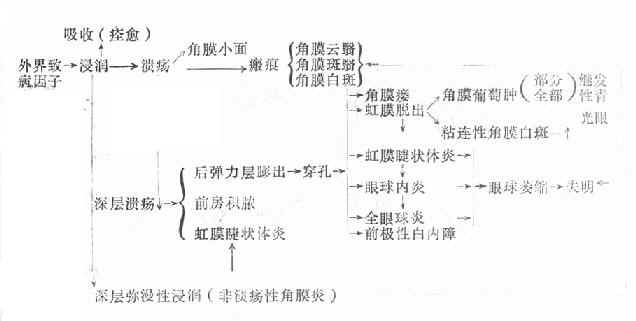

角膜炎发生以后,其病程与病理变化一般可分为三个阶段:即炎症浸润期、进行期和恢复期。炎症病变的转归,一方面取决于致病因素的强弱,机体抵抗力的大小;另一方面也取决于医疗措施是否及时、恰当。兹列表概括如下。

(三)恢复期即炎症的转归阶段。经过治疗,溃疡可逐渐转向清洁,周围健康角膜上皮细胞迅速生长,将溃疡面完全覆盖,在角膜上皮细胞的掩盖下,角膜基质的成纤维细胞增生和合成的新胶原,修补基质的缺损处,角膜溃疡遂告痊愈。角膜中央区溃疡愈合方式多为无新生血管性愈合;周边部溃疡多为有血管愈合。新形成的角膜基质胶原纤维排列紊乱,构成了不透明的瘢痕组织。位于中央区的致密瘢痕可使患眼视力严重丧失。浅层溃疡,仅有角膜上皮层覆盖创面,无结缔组织增生者,则在损伤处形成透明的小凹面,荧光素不染色,称为角膜小面(corneal facet)。(图6-1,6-2)

1、上皮脱落 2.溃疡及前房积脓 3.后弹力层膨出

图6-1 角膜溃疡

图6-2 角膜溃疡进行性演变